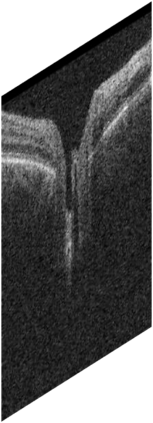

Fairness in artificial intelligence models has gained significantly more attention in recent years, especially in the area of medicine, as fairness in medical models is critical to people's well-being and lives. High-quality medical fairness datasets are needed to promote fairness learning research. Existing medical fairness datasets are all for classification tasks, and no fairness datasets are available for medical segmentation, while medical segmentation is an equally important clinical task as classifications, which can provide detailed spatial information on organ abnormalities ready to be assessed by clinicians. In this paper, we propose the first fairness dataset for medical segmentation named Harvard-FairSeg with 10,000 subject samples. In addition, we propose a fair error-bound scaling approach to reweight the loss function with the upper error-bound in each identity group, using the segment anything model (SAM). We anticipate that the segmentation performance equity can be improved by explicitly tackling the hard cases with high training errors in each identity group. To facilitate fair comparisons, we utilize a novel equity-scaled segmentation performance metric to compare segmentation metrics in the context of fairness, such as the equity-scaled Dice coefficient. Through comprehensive experiments, we demonstrate that our fair error-bound scaling approach either has superior or comparable fairness performance to the state-of-the-art fairness learning models. The dataset and code are publicly accessible via https://ophai.hms.harvard.edu/harvard-fairseg10k.